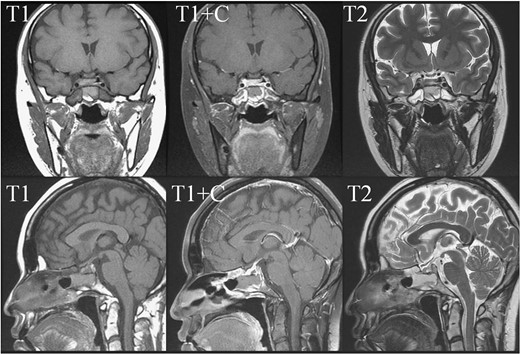

In May 2018, a 28-year-old woman with medical history of sick sinus syndrome and mitral valve prolapse, who just gave birth to a child in April 2018 coming to our Emergency Department with the chief complaint of severe headache and blurred vision for one week. At the Emergency Department, her visual acuity was 0.1 on her right eye and 0.9 on her left eye. Brain CT (computed tomography) scan was checked showing increased soft tissue density over sellar and suprasellar regions, more on the right side. Sellar MRI (magnetic resonance imaging) (Fig. 1) was further arranged which showed a mass with rim enhancement about 2.2 cm ×1.4 cm ×1.2 cm in size located at sella with suprasellar extension with several suspected hemorrhagic foci inside. Under the impression of pituitary apoplexy, she was admitted for further evaluation and management. On admission, her neurological examination showed essentially negative findings except declined right visual acuity; her hormone study showed low level of cortisol (cortisol<1.00 μg/dL) and others were within normal limits. Before surgery, ophthalmologist was consulted again to repeat her ophthalmological examination. The visual acuity of her right eye and left eye improved to 0.8 and 1.0 respectively after the use of steroid. The visual field test showed peripheral defect over the upper visual field of both eyes. Under general anesthesia, she underwent endoscopic endonasal transsphenoidal approach with the removal of tumor and skull base reconstruction. Grossly, the tumor was yellow and soft in consistency and at the end of the procedure, the pituitary gland was well exposed and visible (Fig. 2). After surgery, her vision was subjectively improved; her cortisol level returned to normal (cortisol=16.6ug/dL) and other hormonal data were within normal limits. Histology examination of the tumor (Fig. 3) showed that it composed of spindle to epithelioid cells forming poorly defined lobules and interlacing fascicles, both featuring eosinophilic and oncocytic cytoplasm, with mild nuclear atypia. Immunohistochemically, the neoplastic cells showed TTF-1(+), GFAP(-), EMA(+) Annexin A1(+), and PAS/DPAS(-). Based on the result of histopathology findings and immunohistochemical stains, spindle cell oncocytoma was diagnosed. Before discharge home, her early post-operative sellar MRI (Fig. 4) showed neither residual nor recurrent lesion; she was discharged in a good condition.

Pre-operative sellar MRI. The coronal view (upper row) and sagittal view (lower row) demonstrated a mass about 2.2 cm ×1.4 cm ×1.2 cm in size, located at sella with suprasellar extension. The mass lesion showed low intensity in T1 weighted image, high intensity in T2 weighted image, and rim enhancement after gadolinium injection. Inside the mass, several foci showing high intensity in T1 weighted image, low intensity in T2 weighted image and no enhancement after gadolinium injection were present.